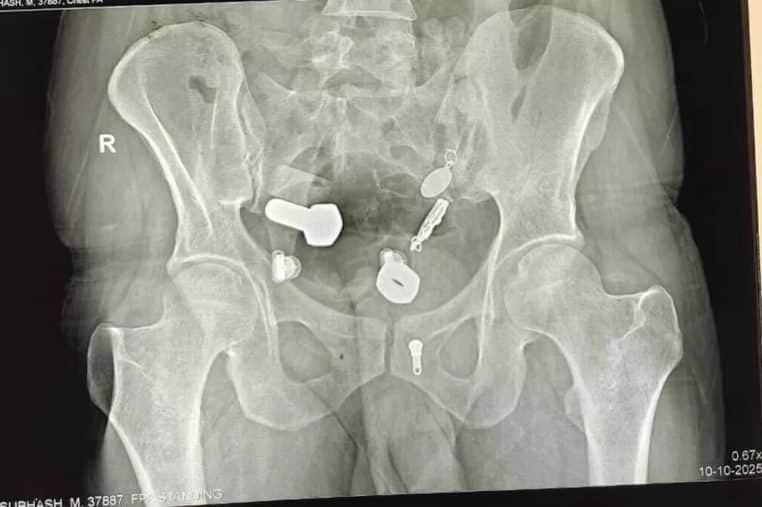

L’homme de 34 ans avait une montre coincée dans son œsophage, ainsi que des fragments de fer, des écrous et des boulons coincés dans son gros intestin. Les médecins ont d’abord essayé de retirer tous les objets métalliques en pratiquant une endoscopie, en vain.

Ils ont finalement fait une petite incision dans son abdomen et lui ont tout retiré lors d’une opération qui a duré trois heures. Les chirurgiens ont partagé une photo de ce qu’ils ont retrouvé dans le corps du patient et c’est impressionnant.